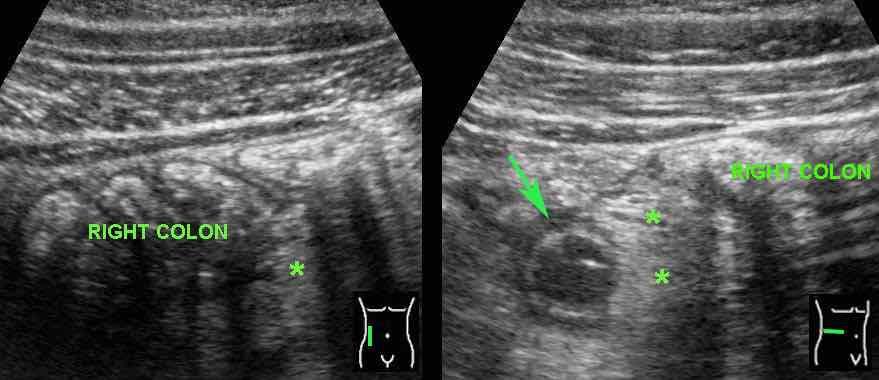

Ở bệnh nhân này, ban đầu dày thành đại tràng lớp dưới niêm mạc được diễn giải là viêm hồi đại tràng do nhiễm trùng bởi Campylobacter hoặc Salmonella.

Đặt đầu dò ở vùng hông phải cho thấy ruột thừa đang viêm (mũi tên) được bao quanh bởi mỡ đang viêm (*).

Sự hiện diện của mỡ đang viêm tự nó là dấu hiệu then chốt, vì đây là dấu hiệu không bao giờ gặp trong viêm đại tràng do nhiễm trùng.